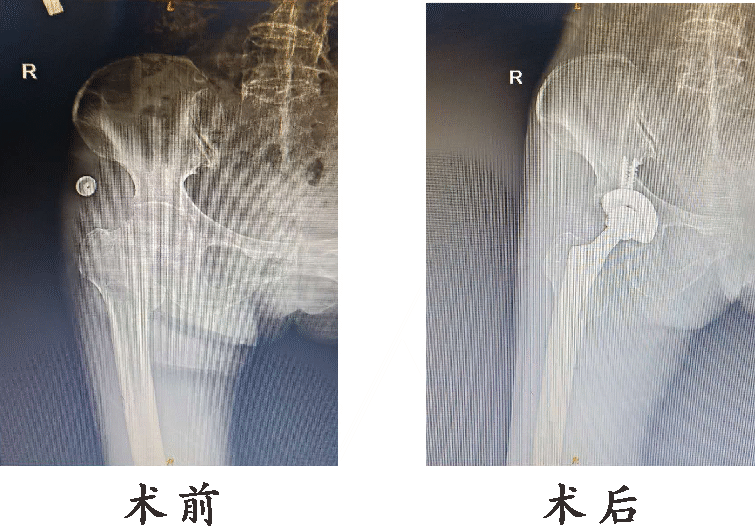

●髋关节置换术

髋关节置换又称作人工髋关节置换,是将人工假体,包含股骨部分和髋臼部分,利用骨水泥和螺丝钉固定在正常的骨质上,以取代病变的关节,重建患者髋关节的正常功能,是一种较成熟、可靠的治疗手段。

8、高龄股骨粗隆骨折

优点:

1、髋关节置换可早期下床行走,大大提高患者的生存质量,减少卧床相关并发症。

2、髋关节置换能够大大减少原发疾病,(如:关节炎、股骨头坏死等)所带来的疼痛、功能障碍、跛行等问题。

3、髋关节置换手术技术成熟,疗效确切,手术时间短,手术创伤小,术后功能恢复快。